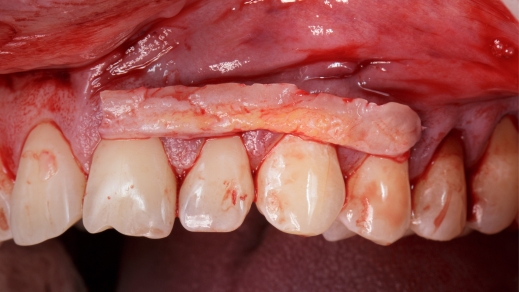

Gum grafting is an oral surgical procedure in which oral surgeons collect healthy tissue from other parts of the mouth or from donors to replace the affected areas. Does it sound scary? But it is not. Modern sedatives help patients relax during the procedure, ensuring it is painless. There are mainly three types of gum grafts: connective tissue grafts, pedicle grafts, and free gingival grafts. Oral surgeons typically determine the most suitable gum grafting procedure after assessing each patient’s oral condition.